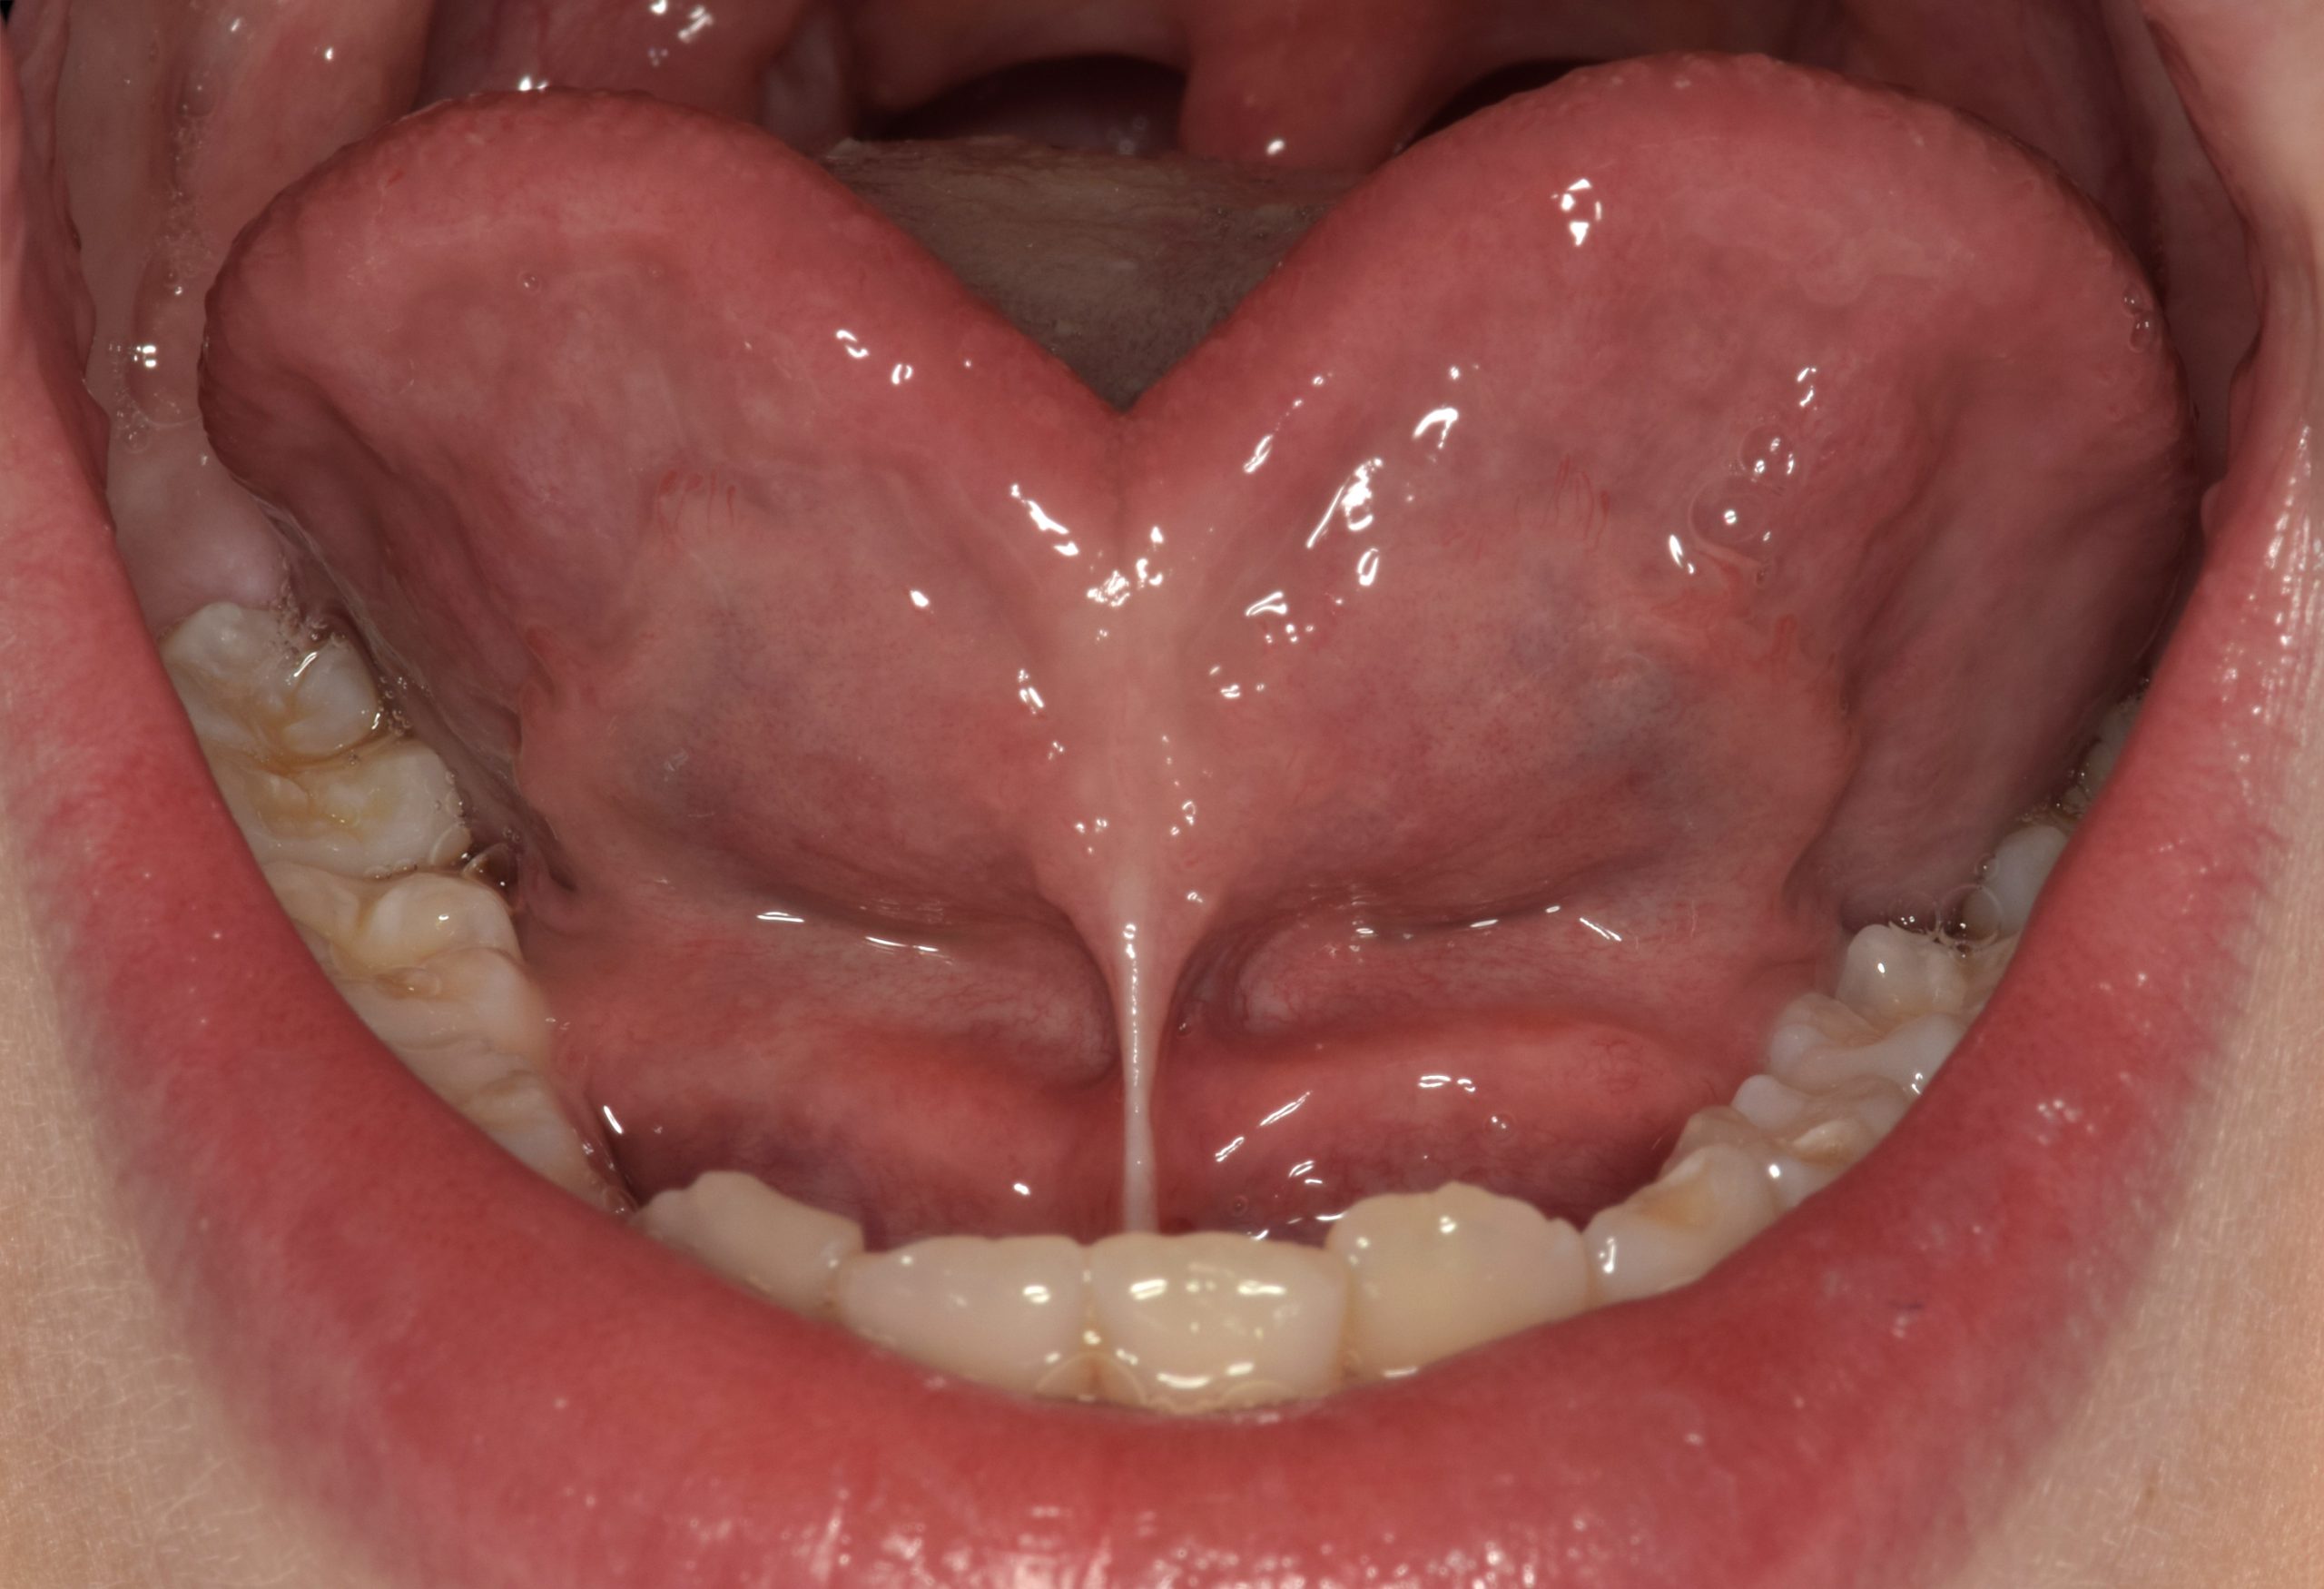

- Rappel d’anatomie linguale et labiale

- Le frein lingual court : conséquences sur la croissance des maxillaires, sur la phonation et sur la posture

- Indications et mesures cliniques pour objectiver, photos

- Identifier avec les outils décrits dans la littérature un frein lingual court ou un frein labial à insertion trop coronaire